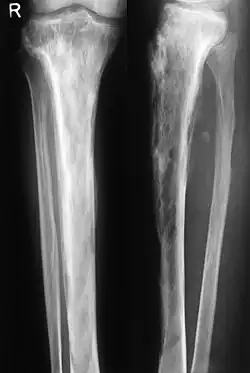

Die Osteodystrophia deformans tritt in der Regel erst jenseits des 55. Lebensjahres auf, verläuft oft symptomlos und wird im Allgemeinen bei einer Untersuchung oder beim Röntgen wegen anderer Beschwerden festgestellt. Sie beginnt als entzündlicher Prozess in einem oder (meistens) mehreren Knochen und ist zu diesem Zeitpunkt schmerzhaft; die Szintigrafie ergibt eine erhöhte Knochenumbaurate. Röntgenbilder des Knochens zeigen unscharfe Aufhellungen.

Im weiteren Verlauf geht die Entzündung zurück und hinterlässt eine dichte, aber unregelmäßige Sklerosierung (kalkreiche Verdichtung) des Knochens, oft auch Deformierungen, druckbedingte Verbiegungen und Auftreibungen der befallenen Skelettelemente, wie eine Wirbelsäulenverkrümmung, einen gewölbter Brustkorb und eine Krümmung der Beine. Bei einer Verdickung der Knochen der Lendenwirbelsäule können Ischiasschmerzen auftreten, die bis ins Bein ausstrahlen (Wurzelkompressionssyndrom).

Wesentlich für die Diagnose ist das Röntgenbild, in dem schon im Frühstadium der Erkrankung die Osteolyse nachgewiesen werden kann. Der erhöhte Knochenumbau kann mittels Knochenszintigraphie nachgewiesen werden.